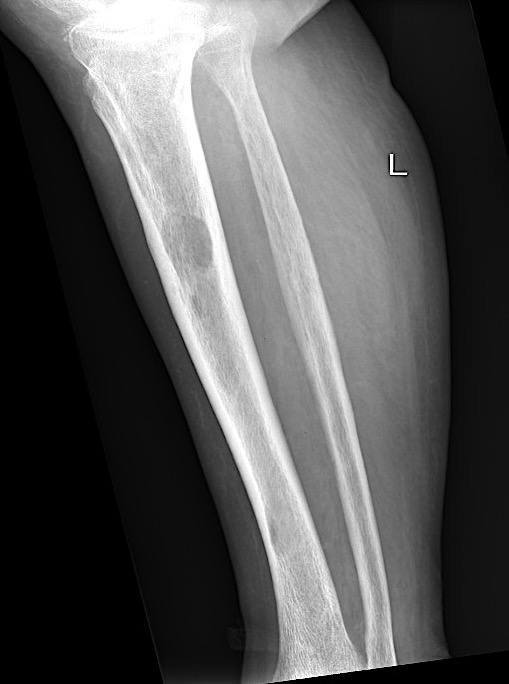

X-ray

1. Punched out lytic lesions

- axial and appendical skeleton

- widely disseminated

- soap bubble appearance

- no sclerotic reaction

2. Diffuse osteopenia

- in 15% to 25% of patients, no discrete lysis occurs

- diffuse osteopenia and osteoporosis are the only skeletal manifestations

4. Pathological Fracture